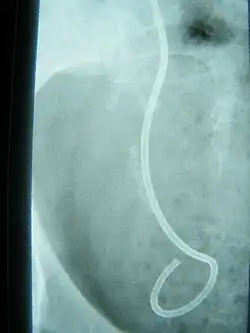

- Steinstraße – unerwünschter Nebeneffekt der extrakorporalen Stoßwellenlithotripsie, bei dem sich Teile des zertrümmerten Steins im Harnleiter sammeln.